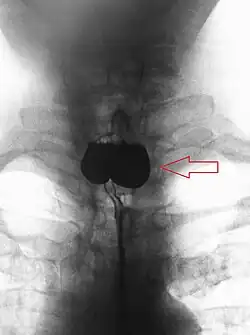

A Zenker's diverticulum, also pharyngeal pouch, is a diverticulum of the mucosa of the human pharynx, just above the cricopharyngeal muscle (i.e. above the upper sphincter of the esophagus). It is a pseudo diverticulum or false diverticulum (only involving the mucosa and submucosa of the esophageal wall, not the adventitia), also known as a pulsion diverticulum.

A combination of the simple barium swallow and a thorough endoscopy will normally confirm the diverticulum.[4]